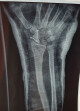

Dice mi médico que se ven avances en las radiografías, pero... que no está seguro de que ya esté todo bien consolidado. Así que, para no cagarla ahora, toca aguantar la escayola un mes más Eso sí, me quitó los piercings, de un tirón con un alicates, todo muy delicado... y se metió con mi moreno obrero.

El médico ha asentido de forma insistente al mirar la placa, y ha dicho que hay que recordar que esto está muy mal, es pronto para decir nada y tal, pero esta placa es para estar contentos. Así que lo estamos.

Dice mi médico que se ven avances en las radiografías, pero... que no está seguro de que ya esté todo bien consolidado. Así que, para no cagarla ahora, toca aguantar la escayola un mes más

@yerena@ElPerroSeLlamabaMisTetas el médico dice que el hueso tiene la forma que tiene que tener y el injerto está integrado, pero el extremo que estaba muerto no ha cogido mucho riego. Por ahora está soldado y pegado donde tiene que estar, pero si no revive más, la unión será frágil. No es un éxito, vamos, pero tampoco un fracaso: si al iniciar movimientos se queda en su sitio, que debería, tendré una mano funcional y sin dolor durante X años. Estamos bastante contentos.

La impresión del médico es que está soldando, pero no soldado, que hay visos de que los trozos comezaron a unirse, pero ninguna garantía de que sigan y culminen. La idea es darle más tiempo y comenzar a reconectar la muñeca. Me ha mandado hacer unos ejercicios en casa y darle otro mes a ver si sigue avanzando, si se queda así a medias o retrocede.